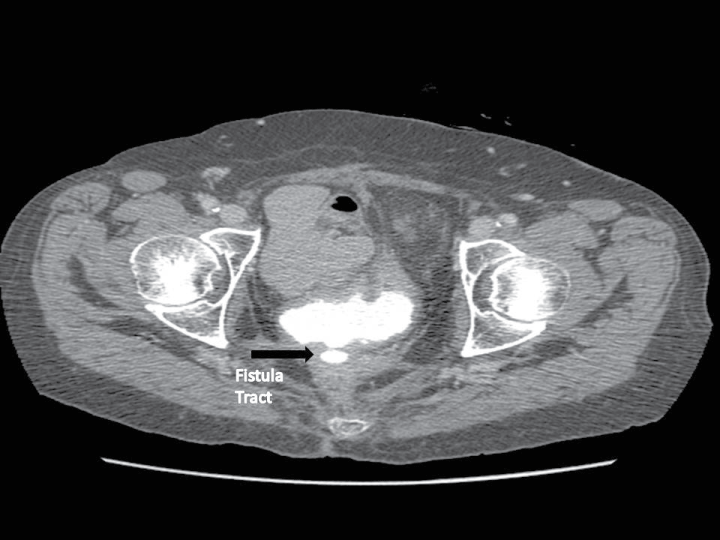

An abdominal VVF repair was utilized for a fistula with multiple tracts, previous failed VVF repair, and/or if inaccessible via vaginal approach (Figure 1). Repairs were approached through an infraumbilical, midline incision and a transperitoneal VVF repair technique was used for all patients. To briefly summarize the technique, cystoscopy was first performed and the fistula tract was intubated with a wire or ureteral catheter. If the fistula was located in close proximity to the ureteral orifices, ureters were also commonly stented so ureteral orifices are not damaged during repair. Lysis of adhesions was then performed to separate abdominal viscera from the posterior peritoneum covering the bladder. Once adequate exposure was obtained, the retropubic space was entered and the bladder was mobilized from the pelvic side walls, leaving the bladder vascular pedicles intact. The peritoneum was next separated from the posterior wall of the bladder down to the vaginal apex. Starting approximately 5 cm above the fistula, the bladder was then bisected along the posterior wall to the fistula tract, as identified by the catheter(s). The edges of the now visible fistula tract were excised from both the bladder and the vagina, back to viable tissue. After resecting the fistula tract, the surgical plain between bladder and vagina was sharply dissected around the excised tract for an additional 2 cm margin. Once adequate tissue was mobilized, the vagina and bladder were then closed independently with at least 2 non-overlapping absorbable suture lines (Figure 2). An interposition flap of peritoneum or omentum was placed between bladder and vaginal closures at the discretion of the treating surgeon.

Figure 1: Example of type of VVF selected for abdominal repair. Patient had developed a VVF after low anterior resection for rectal cancer and pelvic radiation. View Figure 1